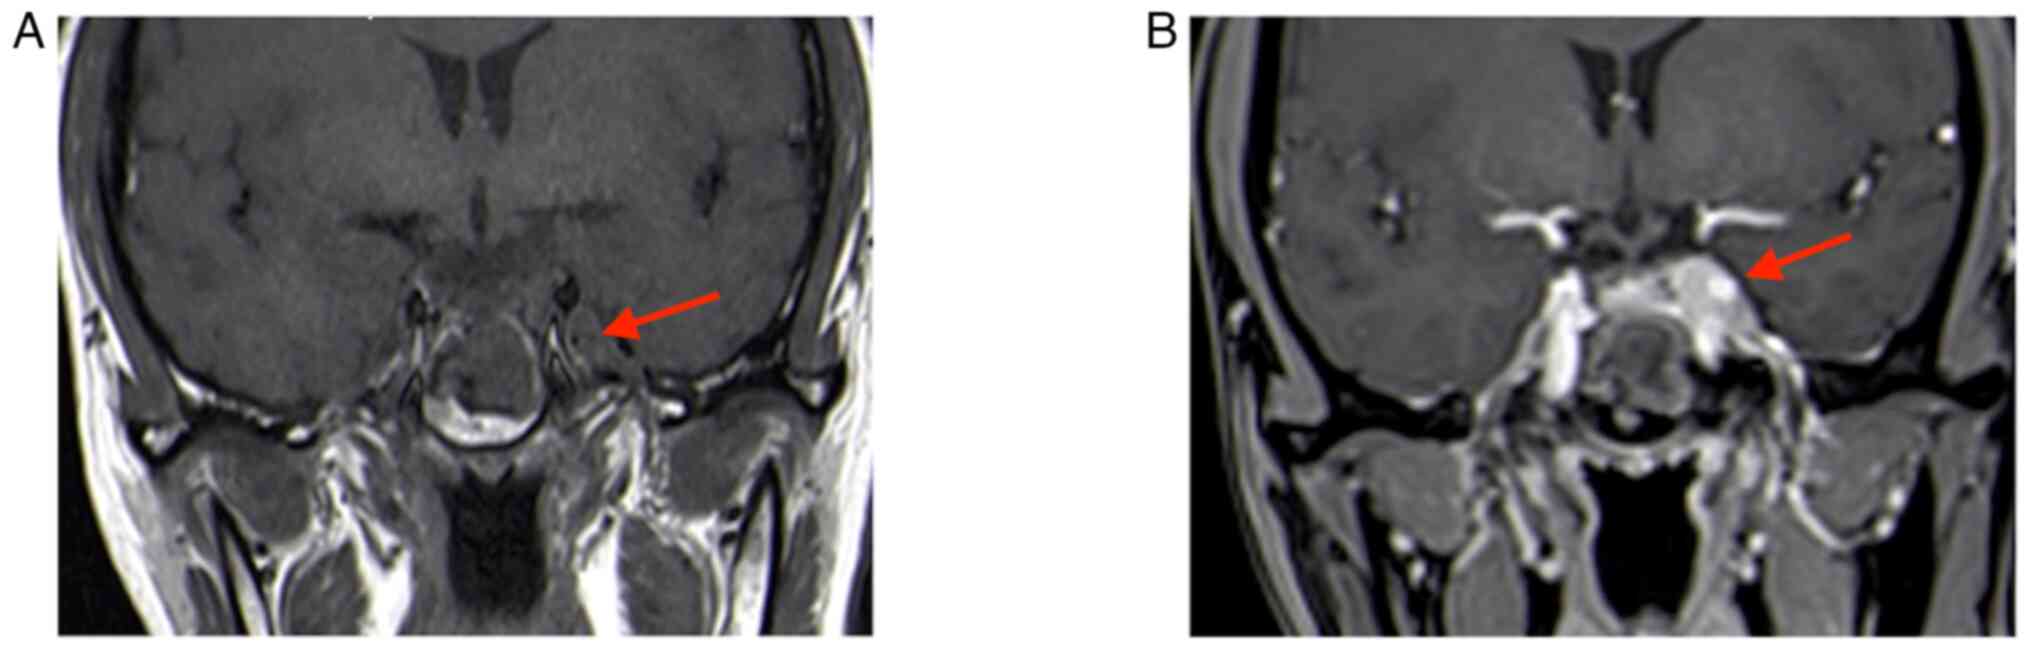

The second MRI (January 2022) performed at the hospital of the present study (the Affiliated Suzhou Hospital of Nanjing Medical University, Suzhou, China) indicated that the tumor grew and was significantly enlarged; it invaded bilateral cavernous sinuses (size, 30×20×18 mm; Fig. 2). Following a thorough evaluation of the patient's condition, a transnasal endoscopic saddle area tumor resection was performed at the hospital of the present study and the tumor was successfully removed. During the operation, the right part of the tumor was soft and could be removed by suction following spatula release; however, the left part was firm and could not be removed by suction; therefore, the tumor was slowly shattered with a curette and removed with tumor removal forceps. The tumor invaded the left cavernous sinus, which was considered to be its origin; bleeding was apparent when the tumor was scraped. Postoperative MRI indicated an extracted cavity with lack of enhancement over the original tumor location, suggesting satisfactory tumor clearance (Fig. 3).

Figure 3.

MRI at 3 days after the second surgery. (A) T2-MRI (the high signal indicated by the red arrow is the fat tissue filled in the surgery). (B) Enhanced T1-MRI coronal image indicating satisfactory tumor resection with no residual (red arrows indicate operation areas). (C) Enhanced T1-weighted sagittal image (the red arrow indicates the pituitary).